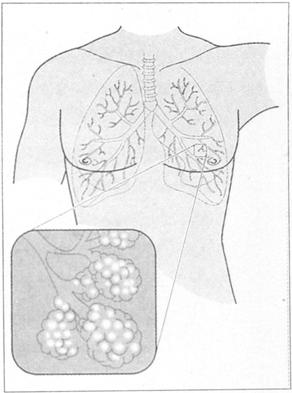

呼吸道包括鼻、鼻咽和喉,向下至肺泡,包括血运,理解肺叶分布对临床评价至关重要(见图63)。右肺分为三个叶,上、中、下叶,而左肺被舌叶(不完整的中叶)分成两个叶,上叶和下叶。

图63 肺叶在体表的分布标志

上叶主要检查前胸,下叶主要检查后背。然而值得提出的是,右中叶疾病仅通过细致的前胸和腋区检查发现,因此右中叶肺炎通常被忽略。